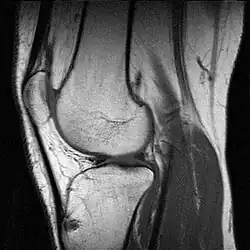

Kreuzbandrisse kommen recht häufig vor. Sie entstehen durch die so genannte Flexions-Valgus-Außenrotations-Stellung. Das heißt, dass das Knie unfreiwillig gebeugt, in die X-Bein-Stellung und nach außen gedreht wird, wobei der Unterschenkel festgestellt ist. Typischerweise entstehen solche Verletzungen beim Skifahren, Handball oder Fußballspielen. Durch das Zerreißen der Bandstrukturen kommt es gleichzeitig zu Gefäßrissen, die eine Blutung in das Kniegelenk (Hämarthros) verursachen. Kreuzbandrisse werden im Schnelltest mittels des vorderen oder hinteren Schubladentests erkannt, d. h. bei gebeugtem Kniegelenk lässt sich das Schienbein gegen den Oberschenkelknochen verschieben und zwar nach vorne (Riss des vorderen Kreuzbands, „vorderes Schubladenphänomen“) oder nach hinten (Riss des hinteren Kreuzbands, „hinteres Schubladenphänomen“). Danach werden die Kreuzbandrisse meist mittels Kernspintomographie diagnostiziert. Behandelt wird ein Kreuzbandriss meistens, indem ein Stück eines anderen Bandes oder einer Muskelsehne entnommen wird, um daraus eine Kreuzbandplastik herzustellen.

Als bildgebende Verfahren werden Röntgenaufnahmen, Sonographie, Arthrographie (kaum mehr angewendet), Magnetresonanztomographie (MRT) und Computertomographie (CT) eingesetzt. Eine Arthroskopie kann zur Darstellung innerer Strukturen angewendet werden.